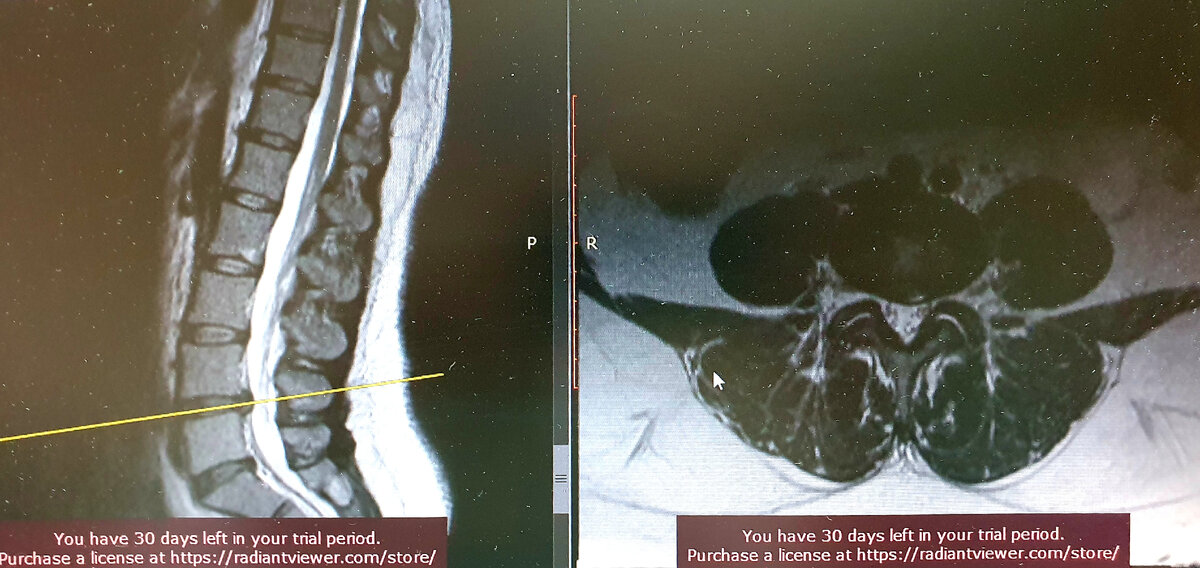

Женщина, 44 года, более 5 лет страдает болями в пояснице ираадиирующие в левую вертельную область (область тазобедренного сустава, если языком пациента), диагностирована грыжа диска L4-L5, которая суживает форамнальные отверстия с обоих сторон, но больше слева.

Грыжа L4-L5, с преобладающим сужением фораминального отверстия слева.

В дополнение к имевшимся жалобам, около 1 года назад появились жалобы на боли в паховой области слева, дообследована и выявлен левосторонний коксартроз 3 степени, при полной сохранности правого тазобедренного сустава.